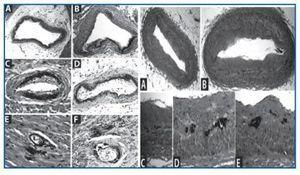

Asimismo, el McCullough25 presenta arterias en las que pueden verse calcificaciones mediales con signos inequívocos de ateromatosis y afectación neointimal (figura 2).

Se han encontrado arterias con calcificación de la media sin ninguna lesión ateromatosa (figura 3).

Figura 2.

Figura 3.